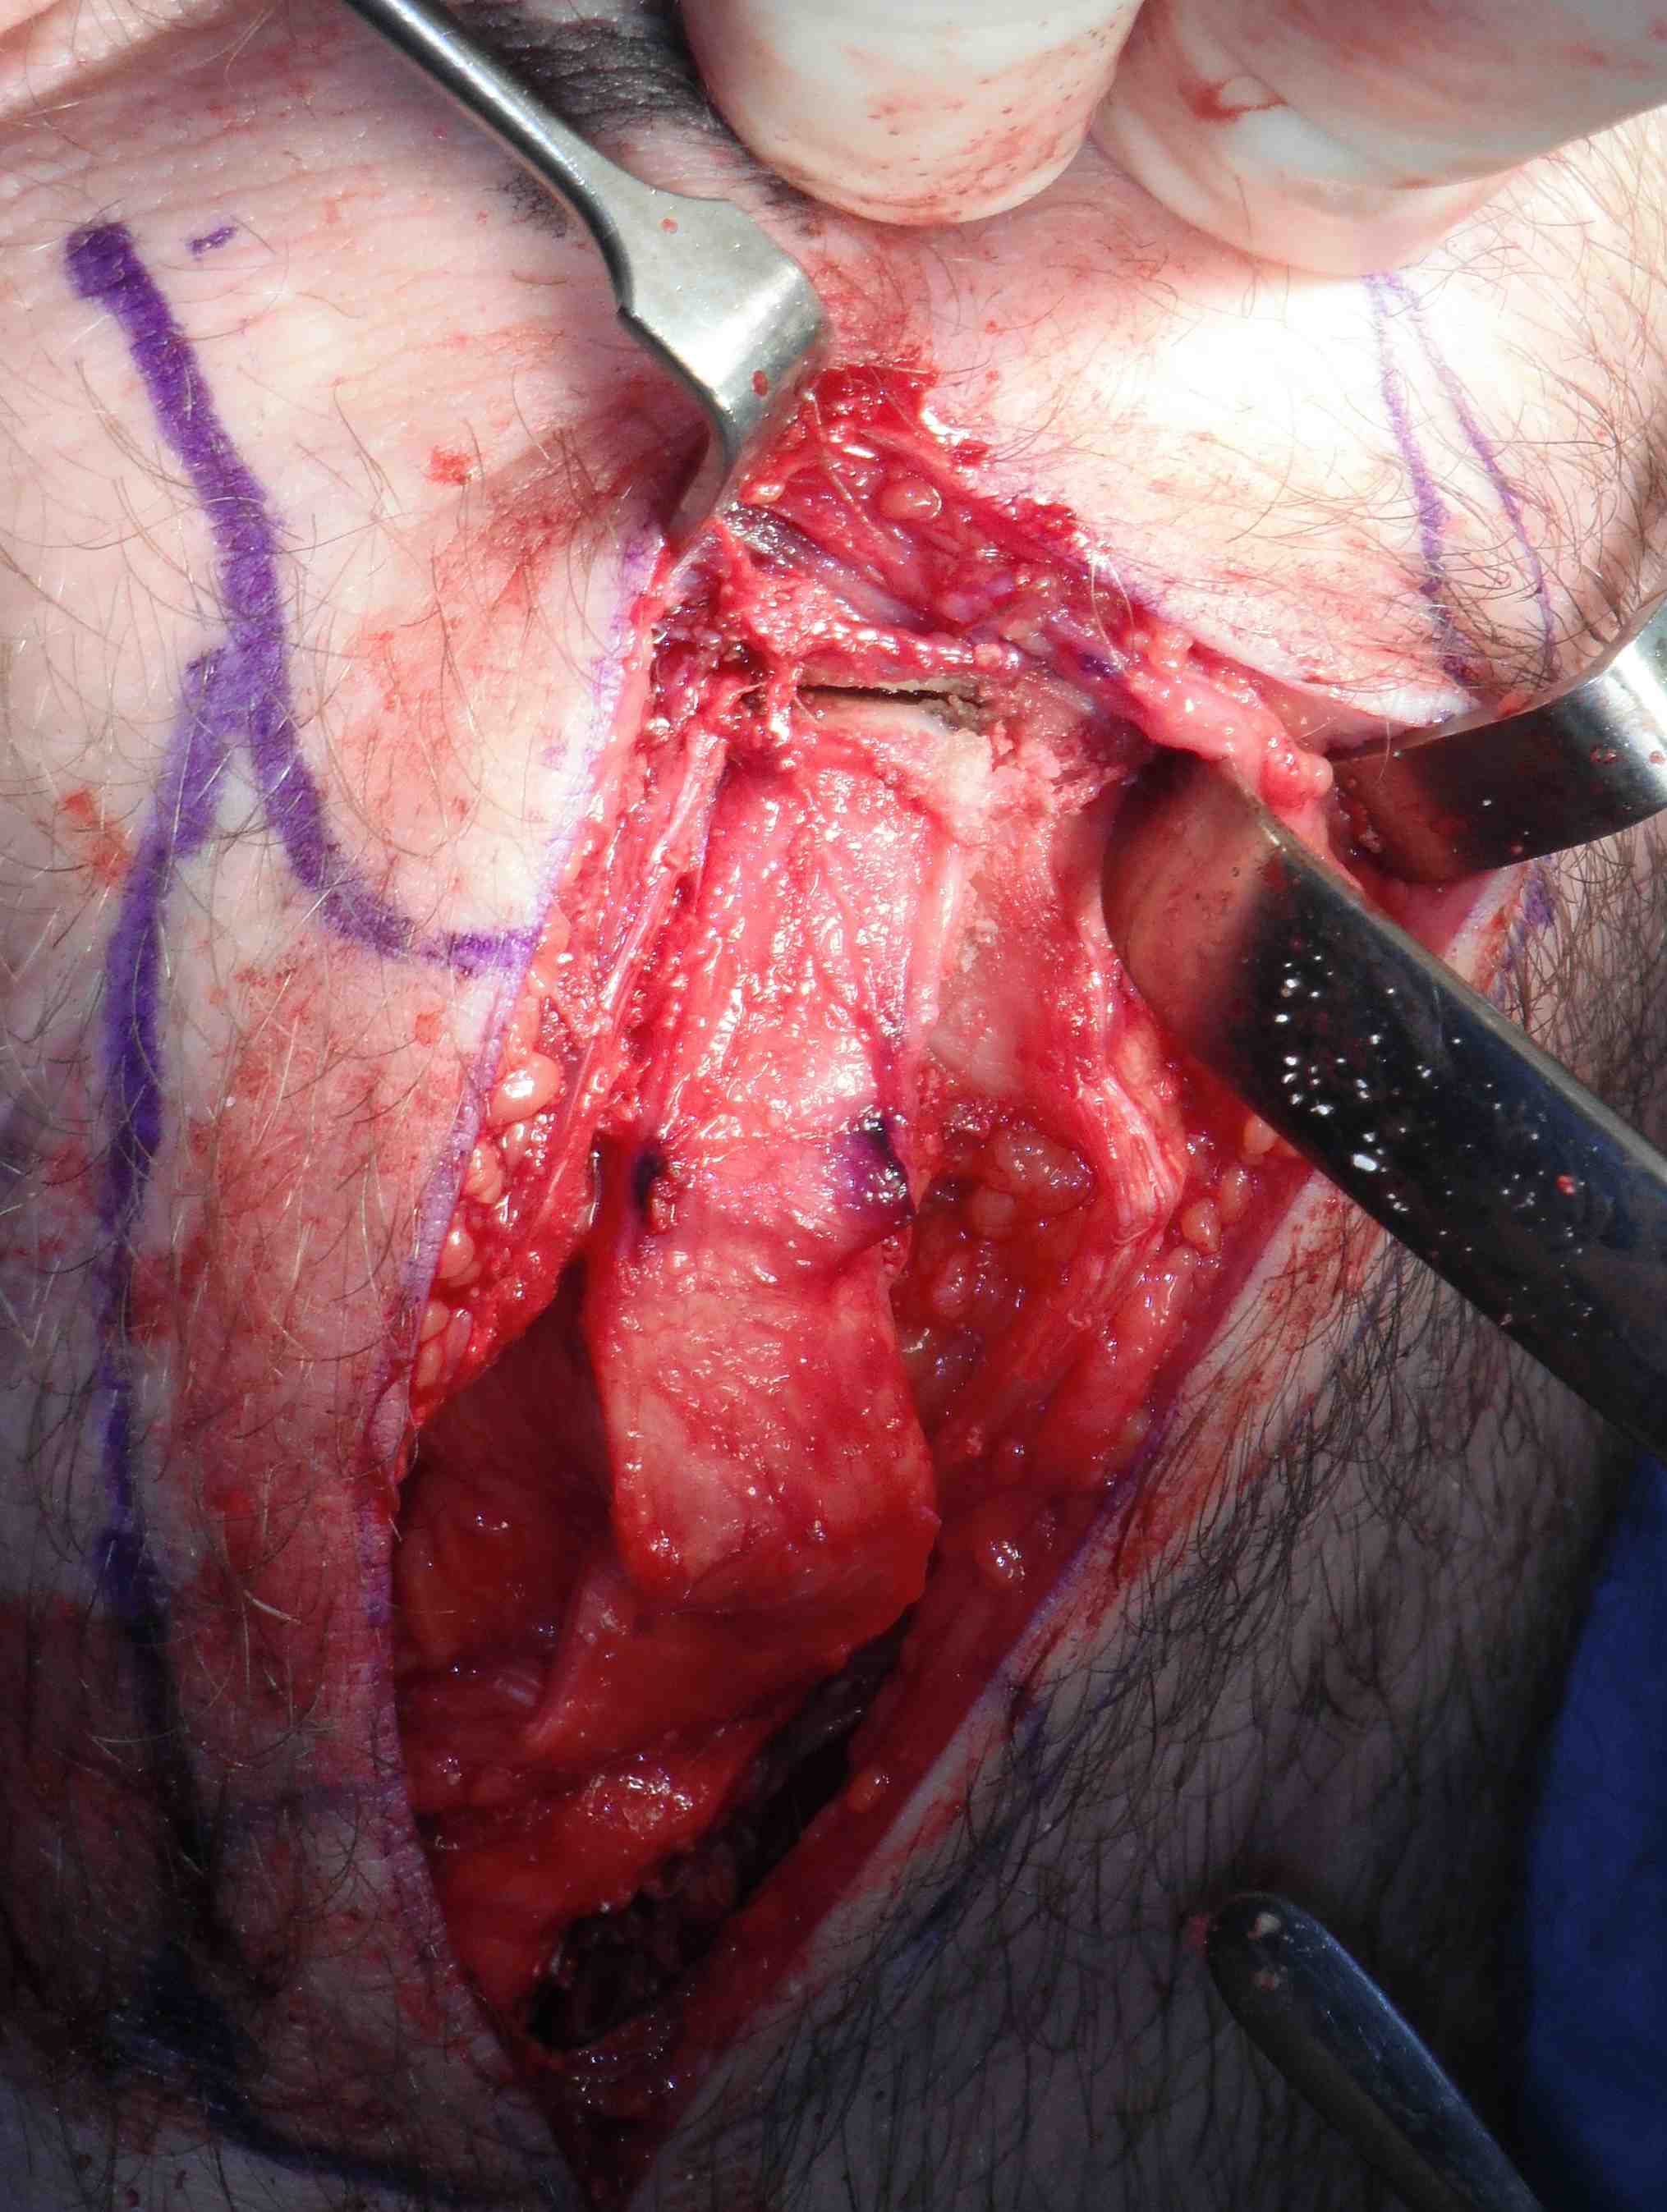

Tunnels

Tibial tunnel

- tibial jig / beath pin / 10 mm reamer

- need to ensure sufficient distance anterior to PCL

- use shaver to clean tunnel, especially entrance

Transtibial femoral tunnel

- need to use 7 mm offset jig to prevent posterior wall blowout

- pass femoral beath pin at 90o

- drill femoral tunnel 10 mm wide

- 5mm deeper than bone graft length

- if bone plug 20 mm long, drill 25 mm

- if bone plug 25 mm long, drill 30 mm

- need to thoroughly clean tunnel of bone debris

- can help to pass acorn reamer twice